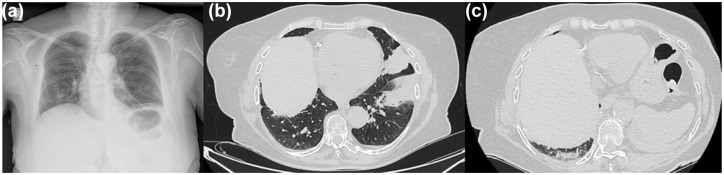

免疫相关神经肌肉疾病是用于治疗癌症的免疫检查点抑制剂(ICIs)罕见且可能危及生命的不良事件。他们往往有一个慢性过程,通常导致永久停止免疫治疗。我们提出一个病例的派姆单抗诱导重症肌无力,只涉及隔膜。患者是一名71岁女性,有IV期肺腺癌病史,在一线化疗免疫治疗完全缓解后,正在接受培美曲塞和派姆单抗的维持治疗。她自上月起主诉直呼,因低氧性呼吸衰竭入院。放射学显示肺体积减小,双肺下野无电区。随后的支气管镜检查排除了感染和癌症复发。肺功能检查显示一种混合性疾病,最大吸气压力严重降低,仰卧位与原位位相比肺活量大幅下降。横膈膜超声检查证实双侧横膈膜功能障碍,患者在睡眠中开始无创通气(NIV),症状得到缓解。神经系统检查未发现其他肌肉受累。重症肌无力综合征的实验室检测显示抗乙酰胆碱受体抗体滴度升高,这证实了重症肌无力的诊断。患者随后接受皮质类固醇、吡哆斯的明和静脉注射免疫球蛋白治疗,并逐渐能够停止补充氧气。在随访中,她的胸片和肺活量有所改善,但她继续使用NIV睡觉。停用了派姆单抗,9个月后,她仍然没有癌症。使用免疫疗法治疗癌症患者的临床医生应该意识到这种罕见的并发症,并在ICI治疗过程中及时调查任何一例矫直,以提供专门的管理。

Immune-related neuromuscular disorders are rare and potentially life-threatening adverse events of immune checkpoint inhibitors (ICIs) used in the treatment of cancer. They tend to have a chronic course that usually leads to the permanent discontinuation of immunotherapy. We present a case of pembrolizumab-induced myasthenia gravis that only involved the diaphragm. The patient is a 71-year-old female with a history of stage IV lung adenocarcinoma under maintenance therapy with pemetrexed and pembrolizumab after a complete response to first-line chemo-immunotherapy. She complained of orthopnea since the previous month and was admitted due to hypoxemic respiratory failure. Radiology showed decreased lung volumes and atelectatic areas in both lower lung fields. A subsequent bronchoscopy ruled out infection and cancer recurrence. Pulmonary function tests revealed a mixed disorder with a severe reduction in maximal inspiratory pressure and a large drop in vital capacity in the supine versus the sited position. Ultrasonography of the diaphragm confirmed bilateral diaphragmatic dysfunction, and the patient was initiated on non-invasive ventilation (NIV) during sleep, which led to symptom relief. A neurological physical examination did not reveal any other muscle involvement. Laboratory tests for myasthenic syndromes showed an elevated titer of the anti-acetylcholine receptor antibody, which confirmed the diagnosis of myasthenia gravis. The patient was subsequently treated with corticosteroids, pyridostigmine, and intravenous immunoglobulin and was gradually able to wean off supplemental oxygen. On follow-up, her chest X-ray and spirometry had improved, but she continued sleeping on NIV. Pembrolizumab was stopped, and she is still free of cancer after 9 months. Clinicians treating cancer patients with immunotherapy should be aware of this rare complication and perform timely investigations in any case of orthopnea in the course of ICI therapy to offer specialized management.